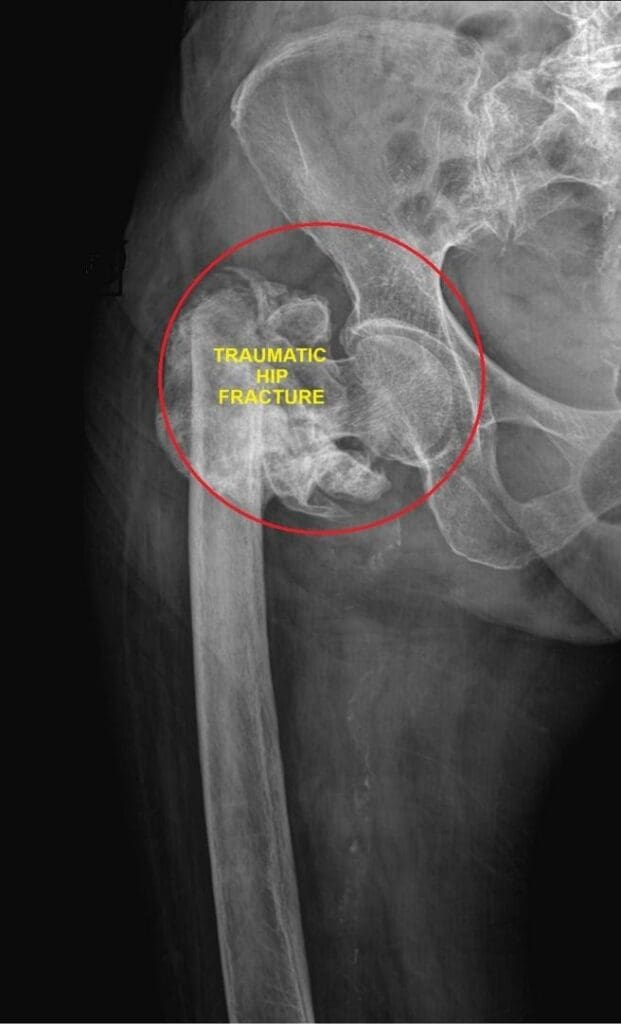

- Hip fractures requiring replacement surgery

- Mortality events following fractures and surgical complications

In fact, for many older adults, a fall is the beginning of a rapid decline in health and quality of life.